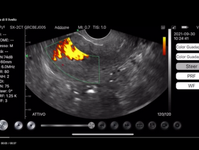

Le sonde ecografiche a ultrasuoni ad alta frequenza wireless Basel Plus sono dotate anche dicolor e power doppler con eventuale analisi...

Le sonde ecografiche a ultrasuoni ad alta frequenza wireless Basel Plus sono dotate anche dicolor e power doppler con eventuale analisi di spettro e si collegano a qualsiasi dispositivo tablet, smartphone e pc, IOS, Android, Windows.